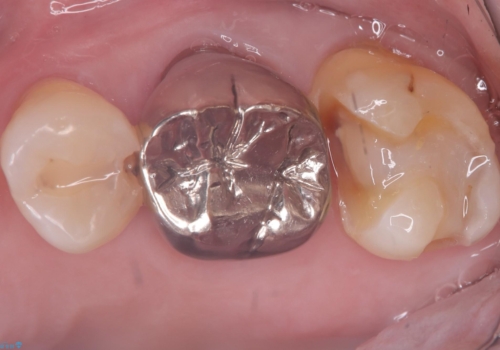

- 主訴:フロスを通したら、詰め物が取れた。適合の良いものを入れたい。

保険適用のメタルインレーが脱離しており、適合重視・咬合力が強いことからゴールドインレーでのやり替えとなりました。

フロスを通しインレーが脱離したことから、インレーと歯質との境に段差(適合不良)があった可能性があり、適合の良さや咬合力による補綴物の破折リスクを考慮し、ゴールドインレーでのやり替えとなりました。